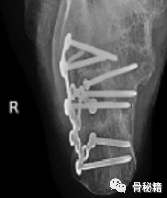

患者被放置在 X 射线可透⼿台上的卧位,⼿台有⻓的悬垂板,可容⼤型 C 臂通过,⼿外科医⽣位于患者后⽅,以便⻣折复位和螺放置提供最佳位置

透视装置与患者的前部和尾部成⼤ 45 度⻆定位,可以位、斜 (Broden) 视,并在垂直位置行透视。